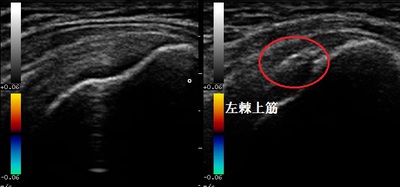

右健側 左棘上筋 超音波長軸像

川越市若葉50代女性、主婦。左肩の痛み、四十肩(五十肩)、石灰沈着性棘上筋腱炎。

超音波検査の結果、左棘上筋内に石灰が沈着している様子が認められました。

し、免疫機能によって炎症症状が起こります。